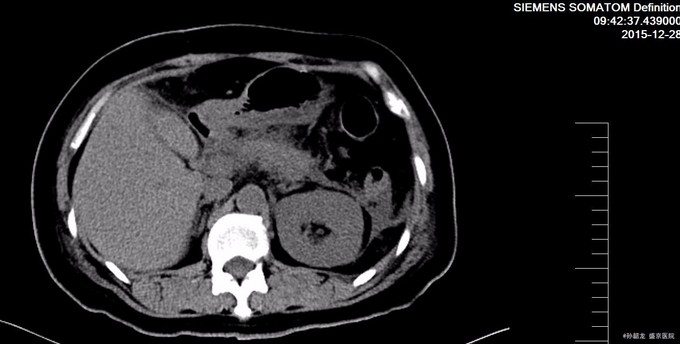

查体: 双侧乳腺缺如。腹平坦,未见胃肠型及蠕动波,腹壁无静脉曲张,左腹部可见经腹直肌切口瘢痕约20cm,以及两点状瘢痕。肝脾肋下未触及,未触及包块,全腹轻压痛,反跳痛,腹直肌紧张。Murphy’s征阴性,肝肾区无叩痛,移动性浊音阴性,肠鸣音4次/分。 辅查: 胰腺CT提示胰腺稍肿胀,轮廓模糊,胰周见模糊渗出及积液,胰腺前方腹腔内渗出。左侧肾前筋膜及邻近腹膜增厚,左侧结肠旁沟内见积液。 肝脏密度仍减低;胆囊内胆汁密度增高。扫描范围左侧胸腔积液。 腹部BUS 提示腹腔积液。 血淀粉酶和脂肪酶明显升高,血甘油三酯和胆固醇升高。